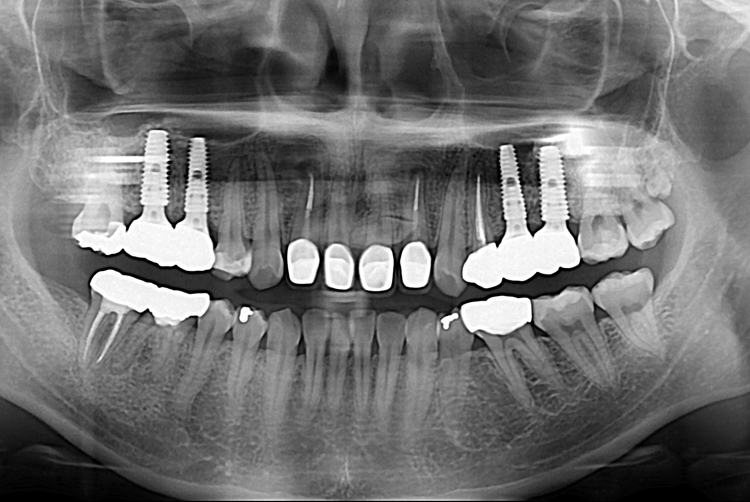

[임플란트] 어금니 임플란트

치료후 : 2018-12-15

세종치과는 많은 환자와 다양한 케이스를 바탕으로

항상 편안한 임플란트 수술을 제공하고자 노력하고,

오래동안 튼튼히 쓸 수 있는 임플란트 수술을 가장 큰 목표로 삼고 있습니다.